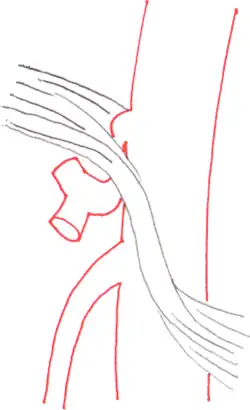

The median arcuate ligament is a ligament formed at the base of the diaphragm where the left and right diaphragmatic crura join near the 12th thoracic vertebra. This fibrous arch forms the anterior aspect of the aortic hiatus, through which the aorta, thoracic duct, and azygos vein pass. The median arcuate ligament usually comes into contact with the aorta above the branch point of the celiac artery. However, in up to one quarter of normal individuals, the median arcuate ligament passes in front of the celiac artery, compressing the celiac artery and nearby structures such as the celiac ganglia.[2] In some of these individuals, this compression is pathologic. It leads to the median arcuate ligament syndrome.[2]

Several theories attempt to explain the origin of pain caused by compression of the celiac artery.[5] One proposes that compression of the celiac artery causes ischemia, or decreased blood flow, to abdominal organs, leading to pain. Another hypothesis is that there is compression not only of the celiac artery but also of the celiac ganglia, and that pain results from compression of the latter.

Further evaluation and confirmation can be obtained via angiography to investigate the anatomy of the celiac artery.[5] Historically, conventional angiography was used, although this has been largely replaced by less invasive techniques such as computed tomography (CT) and magnetic resonance (MR) angiography.[2][5] Because it provides better visualization of intra-abdominal structures, CT angiography is preferred to MR angiography in this setting.[5] The findings of focal narrowing of the proximal celiac artery with poststenotic dilatation, indentation on the superior aspect of the celiac artery, and a hook-shaped contour of the celiac artery support a diagnosis of MALS.[2] These imaging features are exaggerated on expiration, even in normal asymptomatic individuals without the syndrome.[2]

Proximal celiac artery stenosis with poststenotic dilatation can be seen in other conditions affecting the celiac artery.[2] The hook-shaped contour of the celiac artery is characteristic of the anatomy in MALS and helps distinguish it from other causes of celiac artery stenosis such as atherosclerosis.[2] This hooked contour is not entirely specific for MALS however, given that 10–24% of normal asymptomatic individuals have this anatomy.[2]